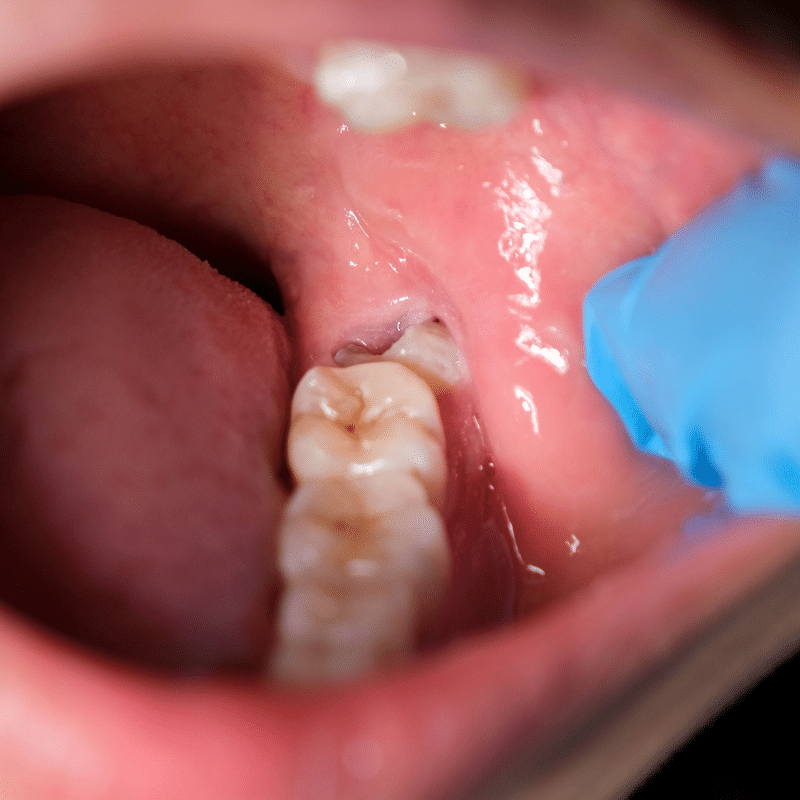

Wisdom teeth typically start developing from the age of 17. During the ages of 19 to 24, the wisdom teeth may erupt into the jaw. In some individuals, the wisdom teeth may never develop. However, others may find that all four have erupted into the jaw. In some cases, the wisdom teeth may come through without causing any problems. In other cases when there is not enough room, the teeth may become impacted. When this occurs infection or inflammation may develop causing serious discomfort and pain.

This is when our dentists can come to the rescue and perform a careful, pain-free wisdom teeth removal in Elsternwick.

For every patient, the wisdom tooth extraction procedure should be planned carefully. We usually recommend a CBCT 3D scan for impacted wisdom teeth. The scan will help us identify potential risks and complications which may arise from the extraction procedure.

In cases where the tooth has become severely impacted, the surgeon will need to make an incision in the gums and also remove some bone as well. The incision will then be closed up with stitches which will aid wound healing. The whole procedure can last up to one hour.